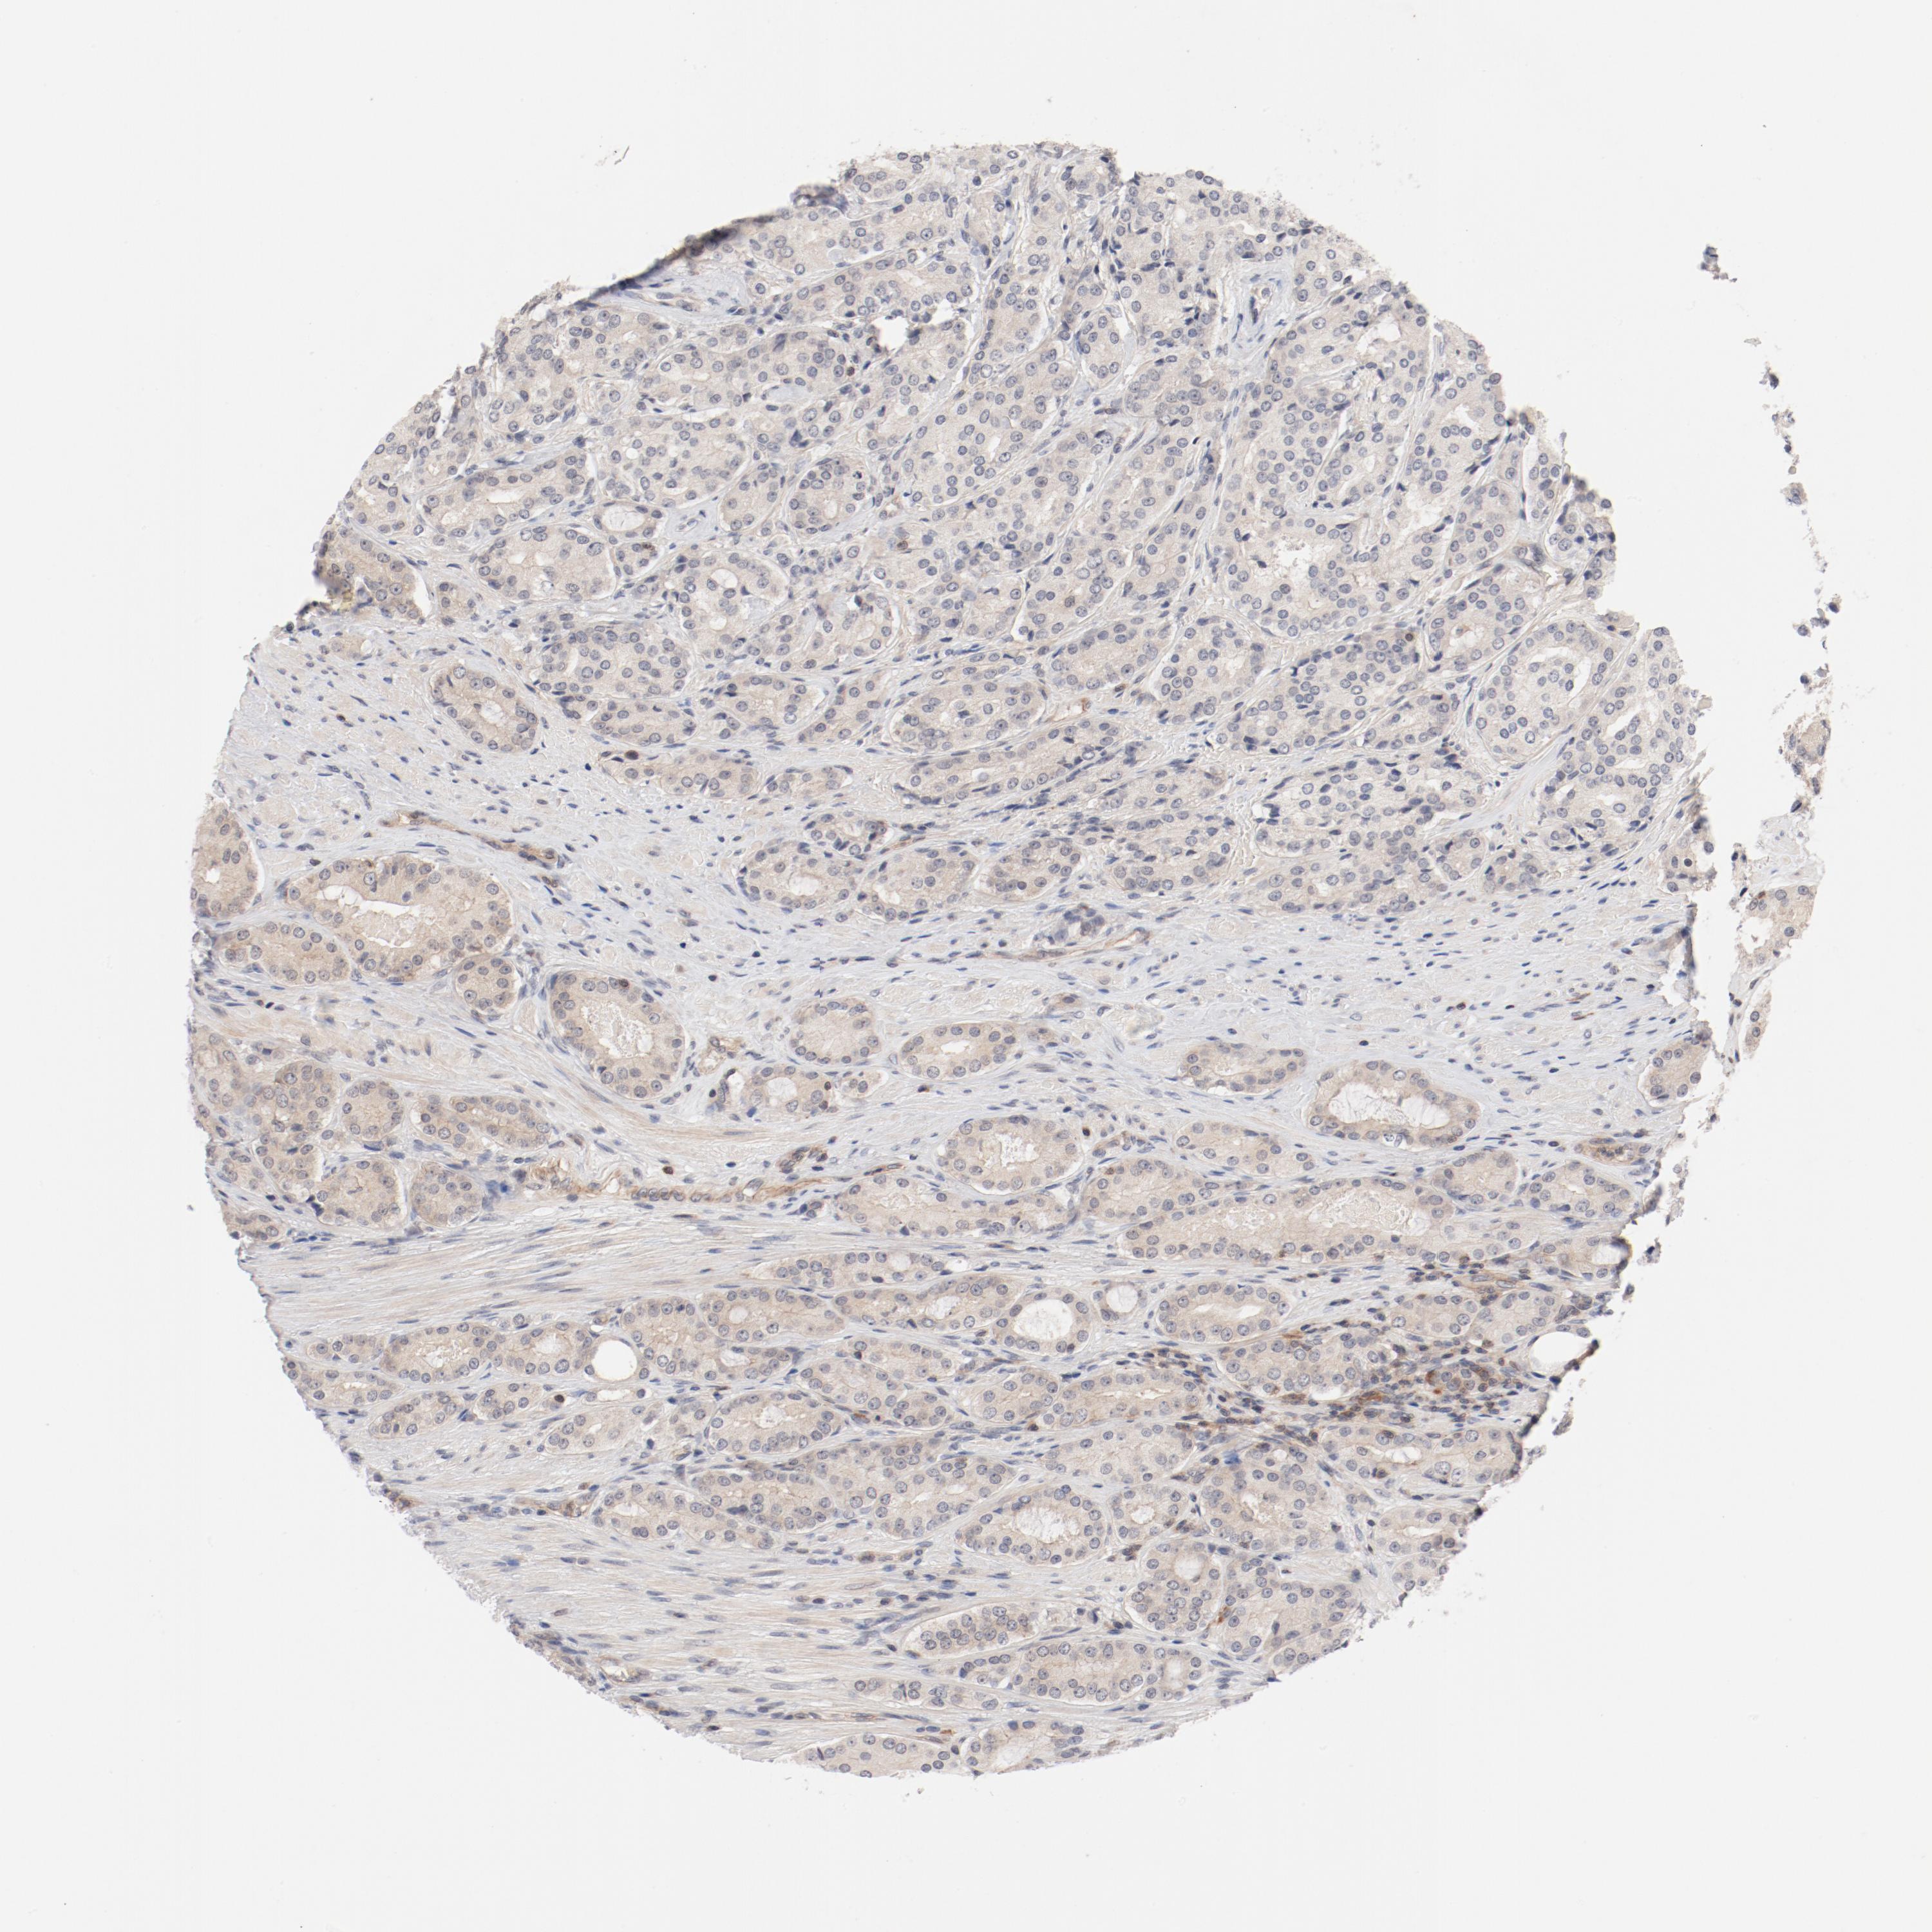

PROSTATE CANCER - Protein expressioni

A mouse-over function shows sample information and annotation data. Click on an image to view it in a full screen mode. Samples can be filtered based on level of antibody staining by selecting one or several of the following categories: high, medium, low and not detected. The assay and annotation is described here.

Antibody stainingi

Antibody staining in the annotated cell types in the current human tissue is reported as not detected, low, medium, or high, based on conventional immunohistochemistry profiling in selected tissues. This score is based on the combination of the staining intensity and fraction of stained cells.

Each image is clickable and will lead to virtual microscopy that enables deeper exploration of all samples and also displays staining intensity scores, fraction scores and subcellular localization as well as patient and tissue information for each sample.

Antibody HPA003866

Staining

High

Medium

Low

Not detected

Intensity

Strong

Moderate

Weak

Negative

Quantity

>75%

75%-25%

<25%

None

Location

Nuclear

Cytoplasmic/membranous

Cytoplasmic/membranous,nuclear

Adenocarcinoma, Low grade

Adenocarcinoma, Medium grade

Adenocarcinoma, High grade